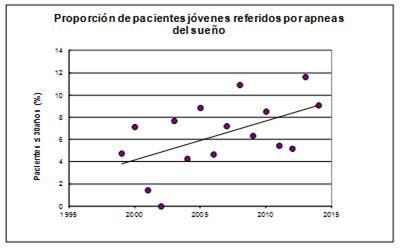

La frecuencia de jóvenes referidos por apneas del sueño se revisó retrospectivamente en el período 1998-2014, en el que fue posible calcular la proporción de pacientes menores de 30 años. De 1676 pacientes del sistema mutual, 139 de ellos tenían menos de 30 años. Esta proporción en 1998 correspondió a 4,8% por año, mientras que en 2014 aumentó a 9,1% (Figura 2).

Figura 2: Proporción de pacientes menores de 30 años referidos por apneas del sueño, según año de la consulta. Se observa un incremento sostenido en la última década.

El aumento de las referencias de jóvenes por apneas del sueño, encontrado en esta revisión, no ha sido reportado con frecuencia23. La mayoría de los estudios de prevalencia se focalizan en poblaciones de más de 30 años y los que incluyen jóvenes son escasos y basados en encuestas de síntomas24).